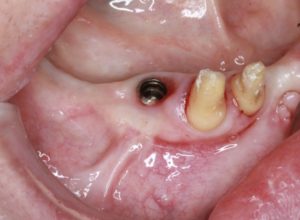

インプラントのライブオペ

今回のライブオペはサイナスなしの6番インプラントの埋入でした。切開線は院長とほぼ同様でした。47度以上で骨壊死するので埋入する時は火傷注意。オペ中はカークランドメスをオペ中多用。先生は基本的に12dを愛用。オステオトームは頻繁に使う。埋入する時コントラは使用しな いで全て手用のみで埋入。インプラントの先にはエムドゲインを少量塗ってから埋入。ヒーリング キャップを入れるときにキャップにテトラサイクリン系の薬をキャップに塗布して治癒を促進させ る。船越先生はストローマンしか使用しない。SLAと使っていて、厳しいケースのみSLAcitveを 使用する。審美領域以外ではなるべくBLよりもインプラントはTLを使いたい(周囲炎的に)